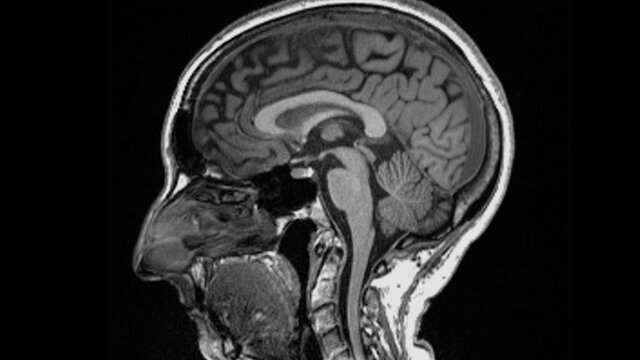

به گزارش شهدای ایران، متخصصان در بررسی های خود تفاوت های قابل توجهی در اسکن MRI افراد، قبل و بعد از ابتلا به بیماری کووید-۱۹ پیدا کردند.به گفته آنان حتی پس از ابتلا به نوع خفیف بیماری، اندازه کلی مغز اندکی کوچک شده و ماده خاکستری کمتری در بخشهای مربوط به بویایی و حافظه وجود داشته است.

در این بررسی سوابق پزشکی ۵۰۰ هزار نفر از حدود ۱۵ سال قبل و داده های مربوط به اسکن آنها قبل از همه گیری، مورد مطالعه قرار گرفت و در دوران همه گیری دوباره از تعدادی از این بیماران اسکن مغزی گرفته شد که این شرکت کنندگان شرایط ذیل را داشتند:

- ۴۰۱ شرکت کننده ۴.۵ ماه پس از ابتلا به عفونت کرونا که ۹۶ درصد آنان به نوع خفیف بیماری مبتلا بودند.

- ۳۸۴ شرکت کننده که دچار بیماری کووید نشده بودند.

کارشناسان انگلیسی با مقایسه نتایج بدست آمده، دریافتند:

- اندازه کلی مغز افراد آلوده به کروناویروس بین ۰.۲ تا ۲ درصد کوچک شده بود.

- از میزان ماده خاکستری در نواحی بویایی مرتبط با بویایی و مناطق مرتبط با حافظه کاسته شده بود.

- افرادی که به تازگی از کووید بهبود یافته بودند، در انجام امور ذهنی پیچیده، کمی مشکل داشتند.